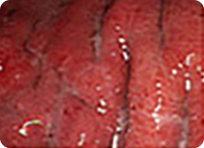

최근 위내시경의 해상도는 아래 사진과 같이 아주 뛰어난 상태로 1mm이하의 작은 병변도 확대해서 관찰이 가능합니다. 따라서 내시경 검사는 정상과 별 차이가 없어 보이는 미세한 조기 위암과, 조기 식도암 및 조기 대장암을 진단하는데 가장 정밀하면서 정확한 방법입니다.

아래 사진과 같이 5x5mm 크기의 작은 사각형을 실제 17인치 모니터에 꽉 차 보일만큼 정확하게 확대해서 관찰할 수 있으며 1mm 눈금보다도 작은 부분도 정확하게 관찰할 수 있을 정도로 정확합니다.

정상 위의 내시경 사진